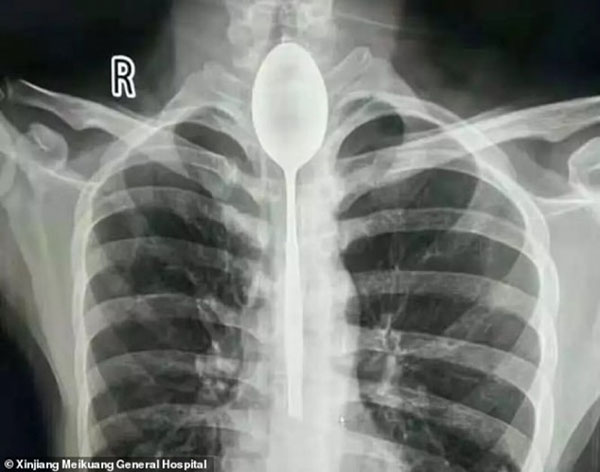

இந்த நிலையில் அவருக்கு திடீரென நெஞ்சு வலி அதிகரித்துள்ளது. உடனே மருத்துவமனையில் அனுமதிக்கப்பட்டவருக்கு மருத்துவர்கள் ஸ்கேன் செய்து பார்த்தனர். அப்போது உணவுக்குழாயில் 8 அங்குல இரும்பு கரண்டி இருப்பதை பார்த்து அதிர்ச்சிடையடைந்துள்ளனர்.

உடனே அவசரமாக அறுவை சிகிச்சைக்கு ஏற்பாடு செய்த மருத்துவர்கள், 2 மணி நேர அறுவை சிகிச்சைக்கு பின் எண்டோஸ்க்கோப்பின் உதவியுடன் கரண்டியை வெளியில் பிரித்தெடுத்தினார். இந்த சம்பவம் தொடர்பாக மருத்துவர் கூறுகையில், ஆரம்பத்தில் கரண்டியை பார்த்து நாங்கள் அனைவரும் ஆச்சர்யமடைந்தோம். தற்போது அறுவைசிகிச்சைக்கு பின்னர் அவர் நலமாக உள்ளார். இன்னும் இரண்டு நாட்களில் வீடு திரும்பிவிடுவார் என தெரிவித்துள்ளார்.